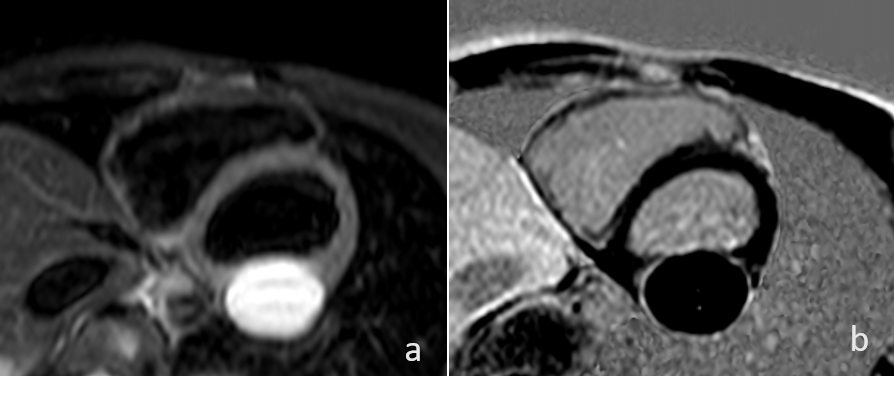

T2-weighted (a) and PSIR (b) imaging SAX: hyperintense cyst and hyperintense (LGE) ring respectively